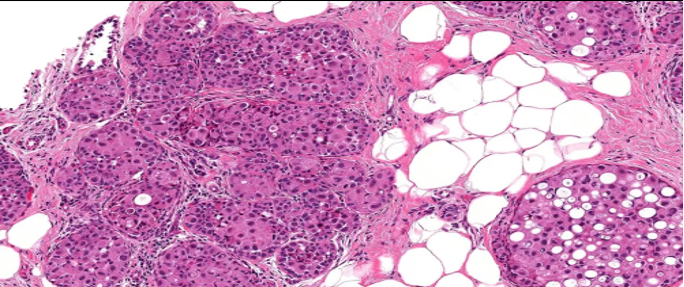

结构特点:轮廓清楚的实性结节纤细的血管轴心。

DCIS样,界限清楚、多个、膨胀性结节状

纤细的血管轴心周围细胞呈栅栏状排列

SPF细胞形态

特征性细胞:形态多样,卵圆形,梭形,多边形,印戒样或浆细胞样胞浆嗜酸性颗粒状,单形性,核低至中级别,染色细腻,可见小核仁核分裂少见(<5/10HPF)肿瘤细胞可有细胞内、外粘液形态单一,呈圆/卵圆形,胞浆淡染、嗜酸性颗粒状嗜酸性颗粒状

SPC+富于细胞的黏液癌